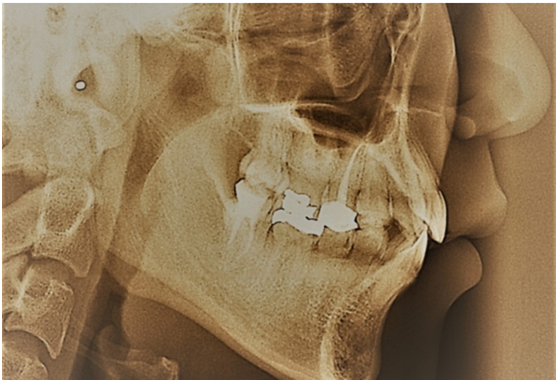

受到贻贝(海虹)能够粘附在坚硬表面机制的启发,圣巴巴拉分校的研究人员开发出一种新型牙科复合材料,为患牙提供更耐久的修复。该研究将广泛应用于填充物、牙冠修复,种植牙及其他相关工作中。

平均而言,牙齿修复体510年左右就要更换。更换时间取决于修复的类型和病人对修复体的使用程度。然而,咀嚼酸性食物和过硬食物、不良口腔卫生、夜磨牙、牙齿本身脆弱以及牙齿护理工作不足等因素都可能导致修复体过早失效,从而再进行一次昂贵而不愉快的修复经历。

Ahn说,充填体脱落的主要原因之一是充填体与周围牙齿间粘结的脆性破坏。他解释说:“所有的牙科复合材料都含有微颗粒以增加其刚性,防止其固化过程中的收缩。但是,当复合材料变硬时,它也会变得更脆。”

在足够的压力或磨损下,充填体会有裂纹形成,然后辐射到整个充填体中。或者,牙齿和充填体之间的间隙会导致充填失败,包括形成边缘龋等。